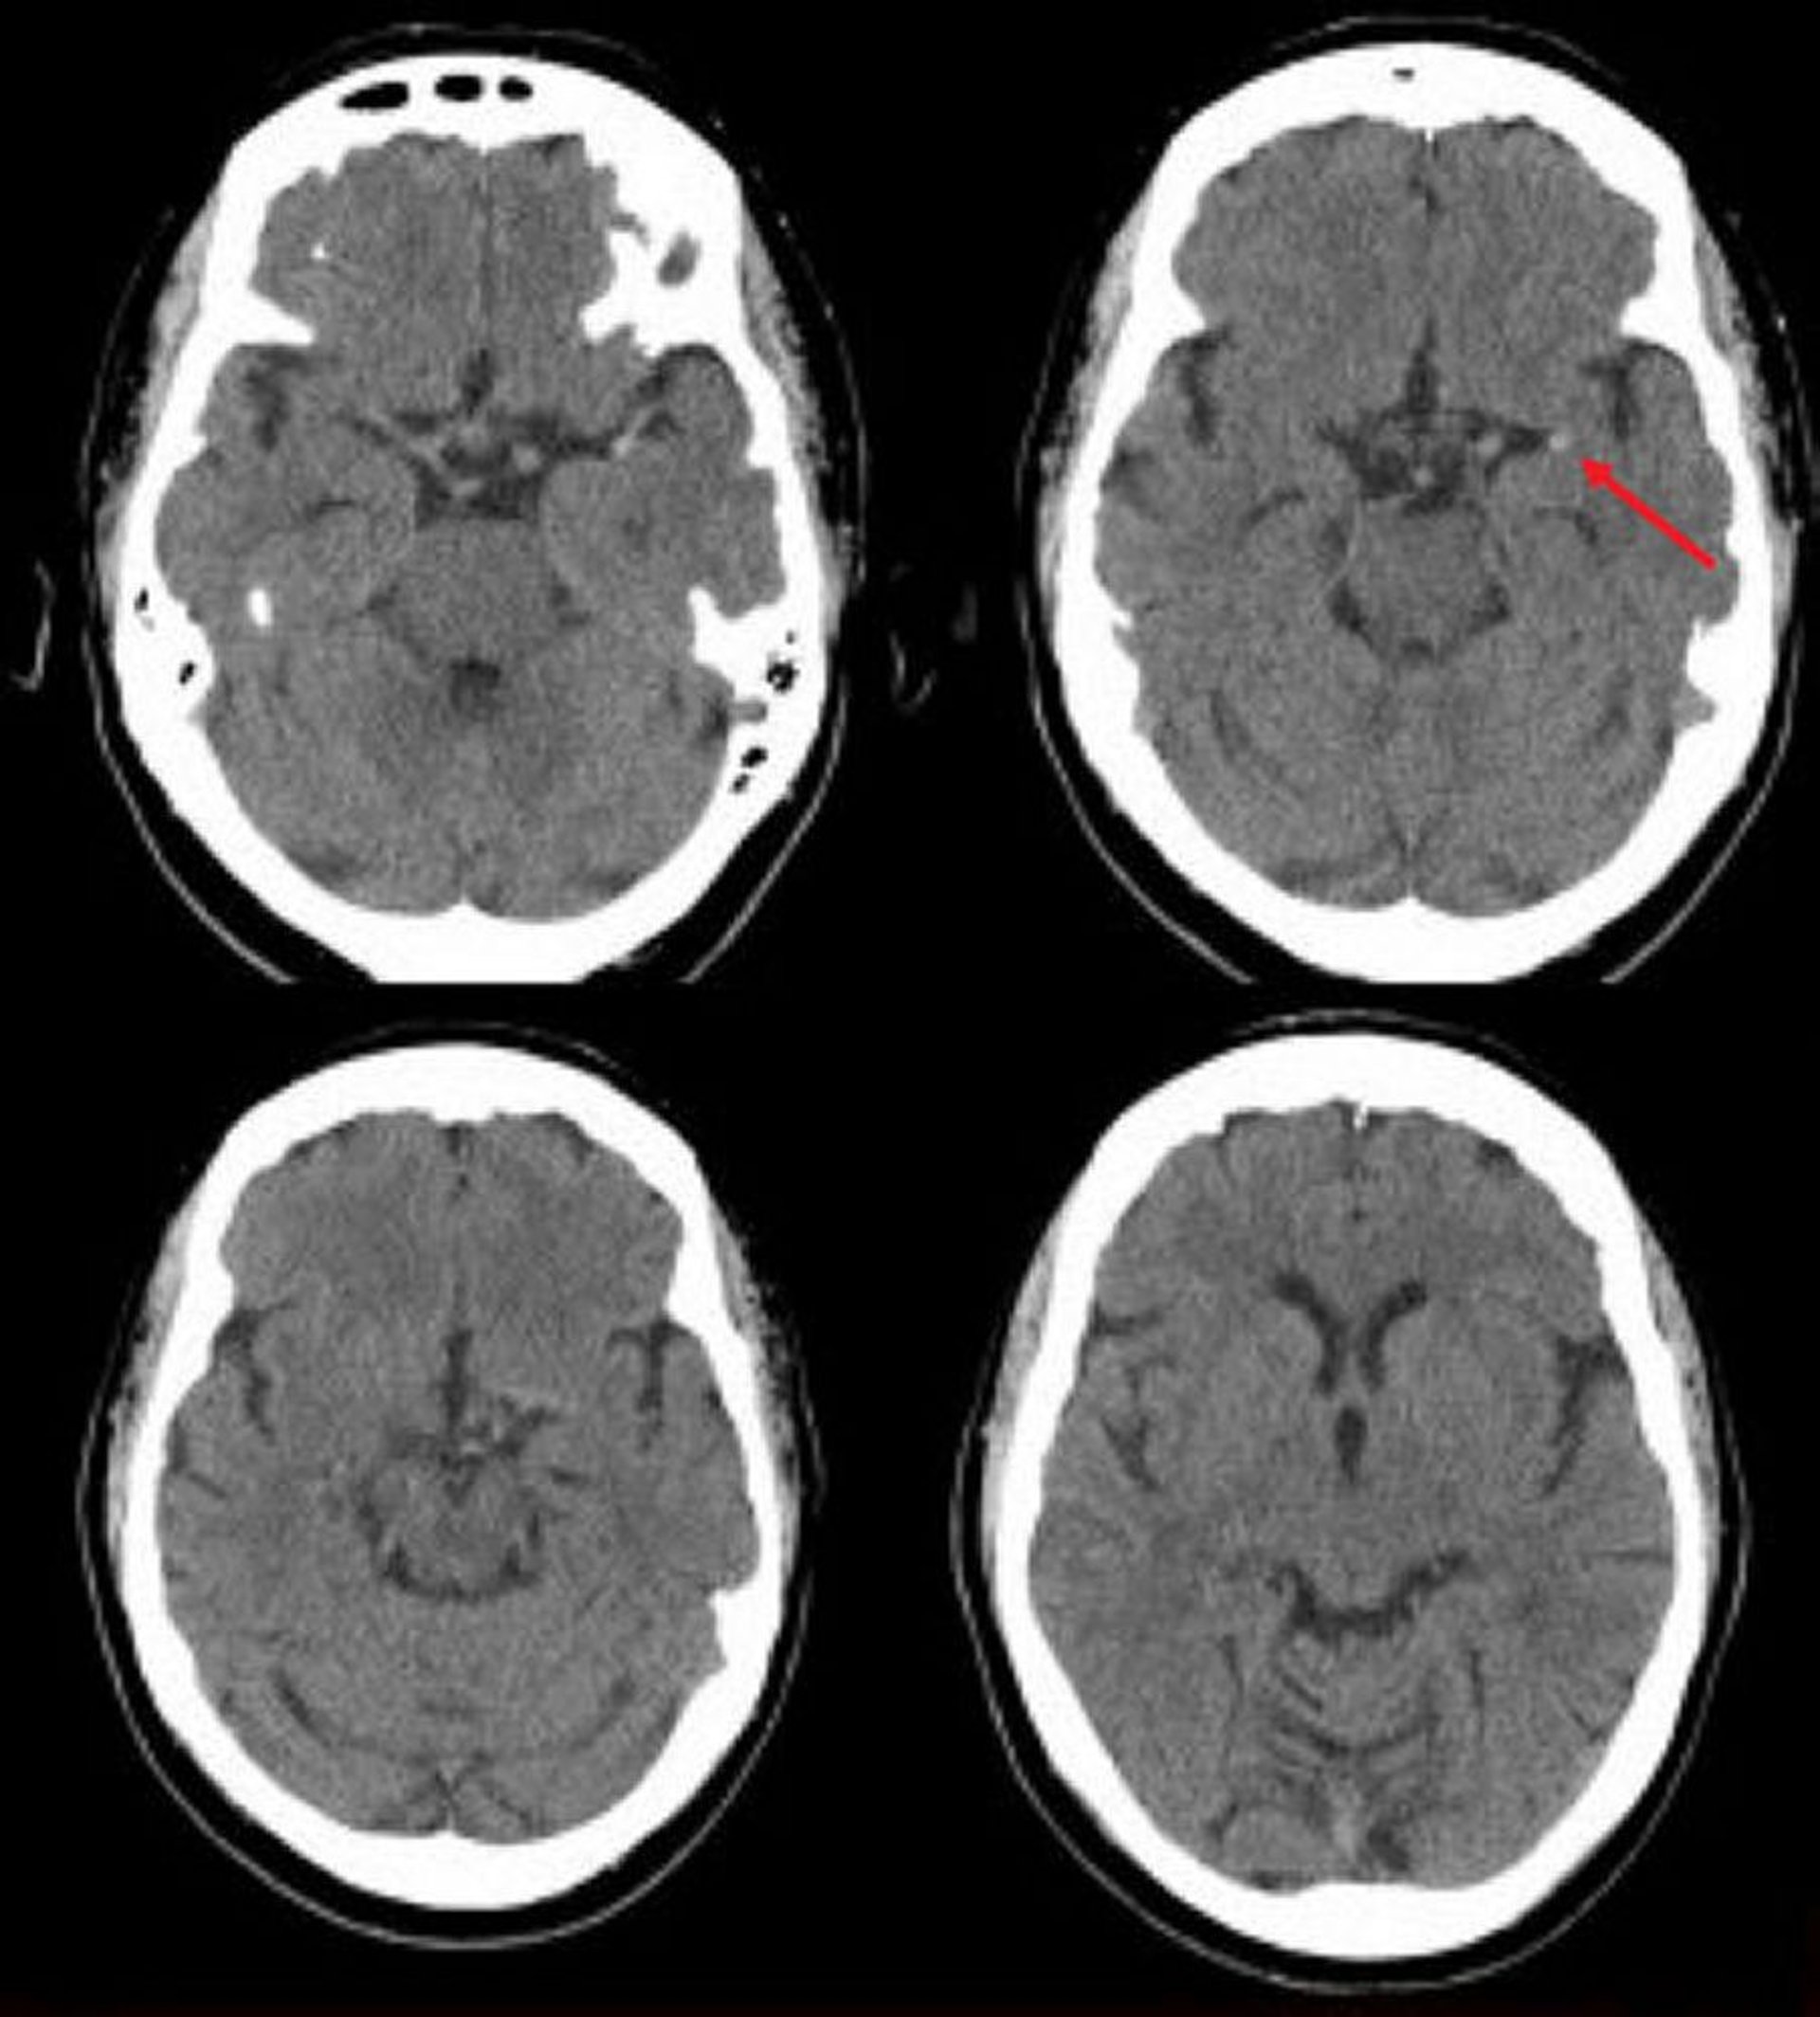

Ischämischer Schlaganfall in der linken mittleren Hirnarterie (CT)

Diese nicht kontrastverstärkte CT-Aufnahme des Schädels zeigt eine hyperdense linke mittlere Hirnarterie. Dieser Befund weist auf ein fokales Gerinnsel in der linken mittleren Hirnarterie hin (Pfeil).

Image courtesy of Ji Y. Chong, MD.